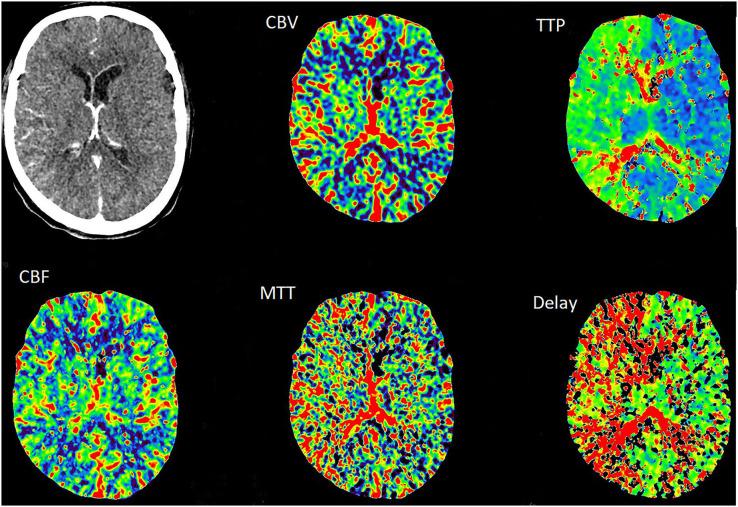

Internal carotid artery dissection (ICAD) results from a tear in the intima or rupture of the vasa vasorum with bleeding within the media resulting in separation of the vessel wall layers and a false lumen. It may cause arterial stenosis, occlusion, or dissecting pseudoaneurysm. Currently, the treatment of ICAD is controversial, including drug therapy and endovascular stent implantation. Simultaneous spontaneous dissection of bilateral carotid artery is rarely reported. We reported a 39-year-old-man with bilateral ICAD. Although the long-term durability of endovascular stent remains to be determined, for ICAD failed with active drug treatment and combined with hemodynamic impairment, early endovascular stent should be considered.

颈内动脉夹层(ICAD)是由于内膜撕裂或滋养血管破裂,血液在中膜内出血,导致血管壁各层分离并形成假腔。它可能导致动脉狭窄、闭塞或夹层假性动脉瘤。目前,ICAD的治疗存在争议,包括药物治疗和血管内支架植入。双侧颈动脉同时自发性夹层的报道很少。我们报告了一名39岁的双侧ICAD男性患者。尽管血管内支架的长期耐久性仍有待确定,但对于积极药物治疗失败且合并血流动力学损害的ICAD,应考虑早期进行血管内支架治疗。